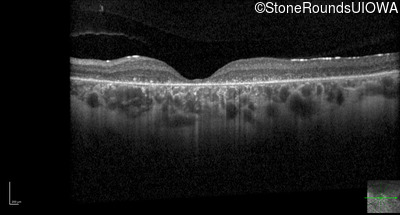

Optical Coherence Tomography - Right - 10/200 sc

Exemplar / OCT Stack